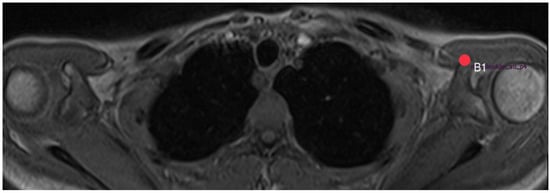

2.3. Acromion Index (Figure 1)